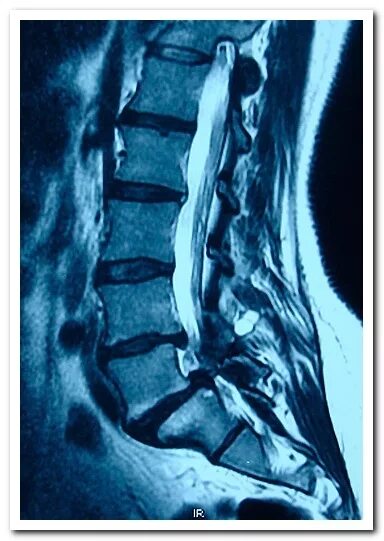

Дегенеративные изменения крестцового отдела